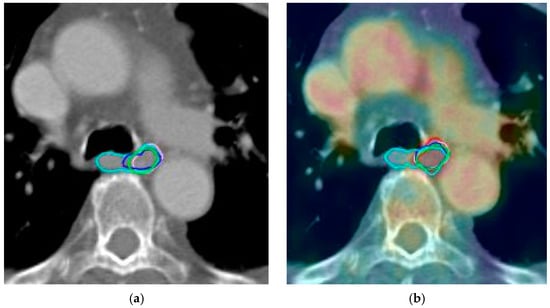

During contouring on PET/CT images, observers initially delineated the GTV on CT images and then corrected the volume as needed using PET images. The GTVPET was defined as 20% of the maximum standardized uptake value (SUV). The PET and CT images were fused, and the visible tumor was contoured as GTV, with adjustments made as needed to include GTVPET (Figure 1).

Figure 1.

Green, cyan, red, purple, blue and magenta lines represent delineations of the tumor by each observer in case 9 based on: (a) computed tomography alone; (b) positron emission tomography with computed tomography; (c) computed tomography with fused magnetic resonance; (d) positron emission tomography with computed tomography and magnetic resonance.